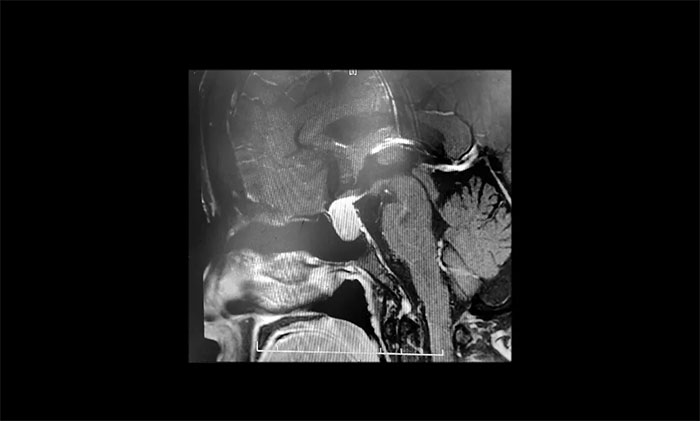

听到脑袋里长了肿瘤,张阿姨一家人非常紧张,为谨慎起见,张阿姨在家人陪同下,特地到上海专业脑科医院求医复诊。经鞍区MRI平扫+增强检查显示:蝶鞍显著扩大,鞍区见T1、T2中等信号实性肿块样占位病变,垂体柄明显缩短,病变总矢横高径约1.2*1.6*1.8cm,病变突破鞍膈,向鞍上生长,推移视交叉,视交叉受压、上抬。

▲ 垂体大腺瘤超蝶鞍生长

神经外科6B病区主任潘仁龙主任指出,患者垂体瘤较大,属于垂体大腺瘤,患者的头痛就是垂体瘤在作祟。并且肿瘤已经压迫视神经,手术指征明确,无明显手术禁忌,应及时手术,否则往后发展患者视力也会受损。